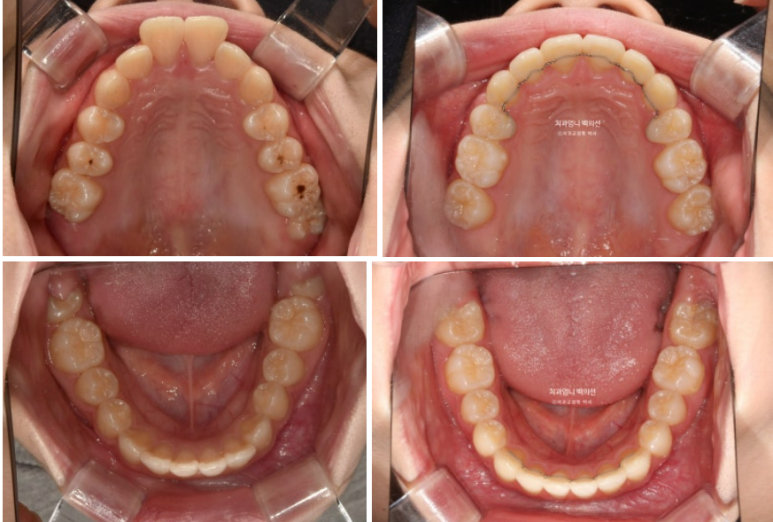

23.09

돌출이 위에만 국한되어 있어 위에만 작은어금니 2개 발치 후 교정하기로 했습니다.

24.06

발치공간은 절반정도 닫혔습니다.

아래는 비발치로 배열 진행중입니다.

1년 9개월 후 치료를 마쳤습니다.

25.06

중심선은 잘 맞습니다.

교합은 좋습니다.

간혹 작은어금니 발치교정은 4개를 빼야 교합이 맞지 않나에 대한 질문을 듣는데 위에만 돌출인 경우 위에만 2개 빼는 교정도 좋은교합으로 마무리 되는 교정이랍니다.

그런데 파란화살표에 교정 중 양치가 잘 안되던 부분에 하얀 자국이 보이시죠. 브라켓이 붙어있던 네모모양을 제외한 주변이 초기충치로 얼룩덜룩 해진 모습입니다.

앞으로 관리가 잘 된다면야 큰 문제는 없겟지만 일부는 레진치료가 필요합니다.

교정 중 양치가 어려운 브라켓 주변 등은 월진료 올때마다 병원에서 스케일을 매번 하고 불소도포도 하고 있지만 평소에 양치질이 안되면 장사 없습니다.